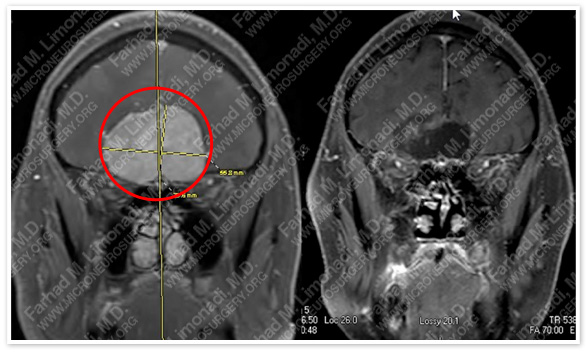

Post-op Imaging

Before Operation                                                       After Operation

Post-op MRI shows complete resection of the tumor with no injury to surrounding neurovascular structures.